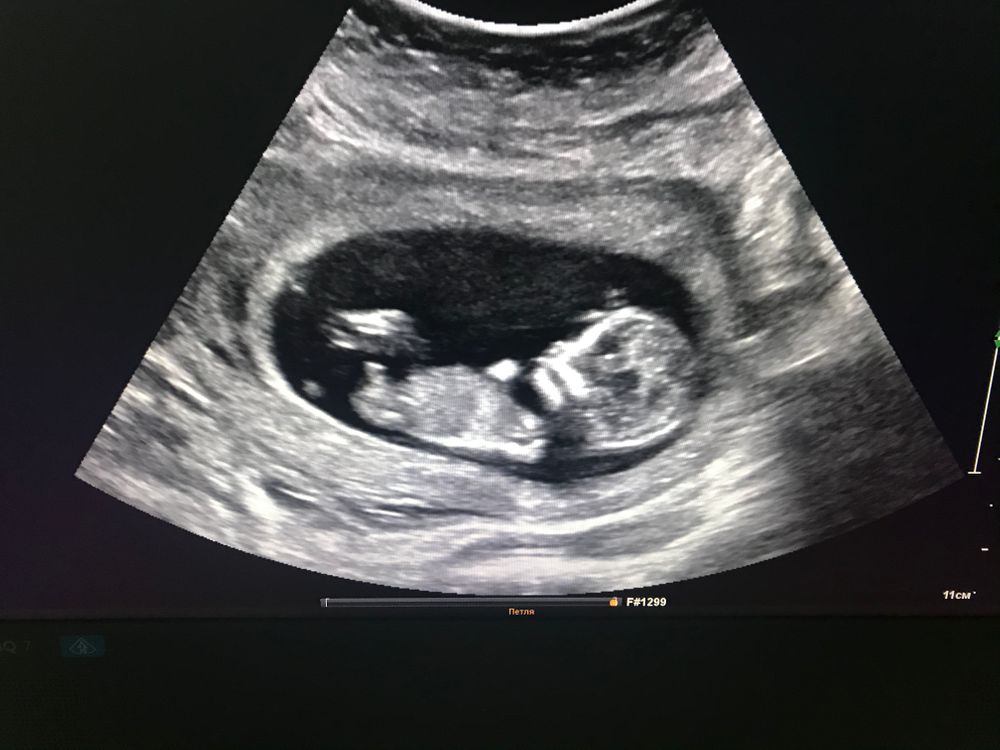

Носовая кость и толщина воротникового пространства на 12 неделе

Скрининг был в 12.4, но малыш немного опережал по размерам, поставили 13.1 ТВП 1.3, нос 2.2 Сделали расширенный НИПТ, т.к. я возрастная. Риски низкие!

В 12.4 нос 3мм, ТВП - 1.6мм. Носик у дочки курносый, небольшой.

У обоих детей носовая кость 1.8 мм.

Самое главное что носовая кость есть, а размер ее это не важно.

Норма по носовой кости от 2 мм. У нас была 2,5. ТВП 1,8 - не мало, нормально абсолютно) у дочери в 12 недель ТВП была 0,9 мм.

У этого синдрома носовой кости не обнаруживают, и много других факторов. У вас большой, хороший носик))))

Заключение узи Не даёт покоя носовая кость